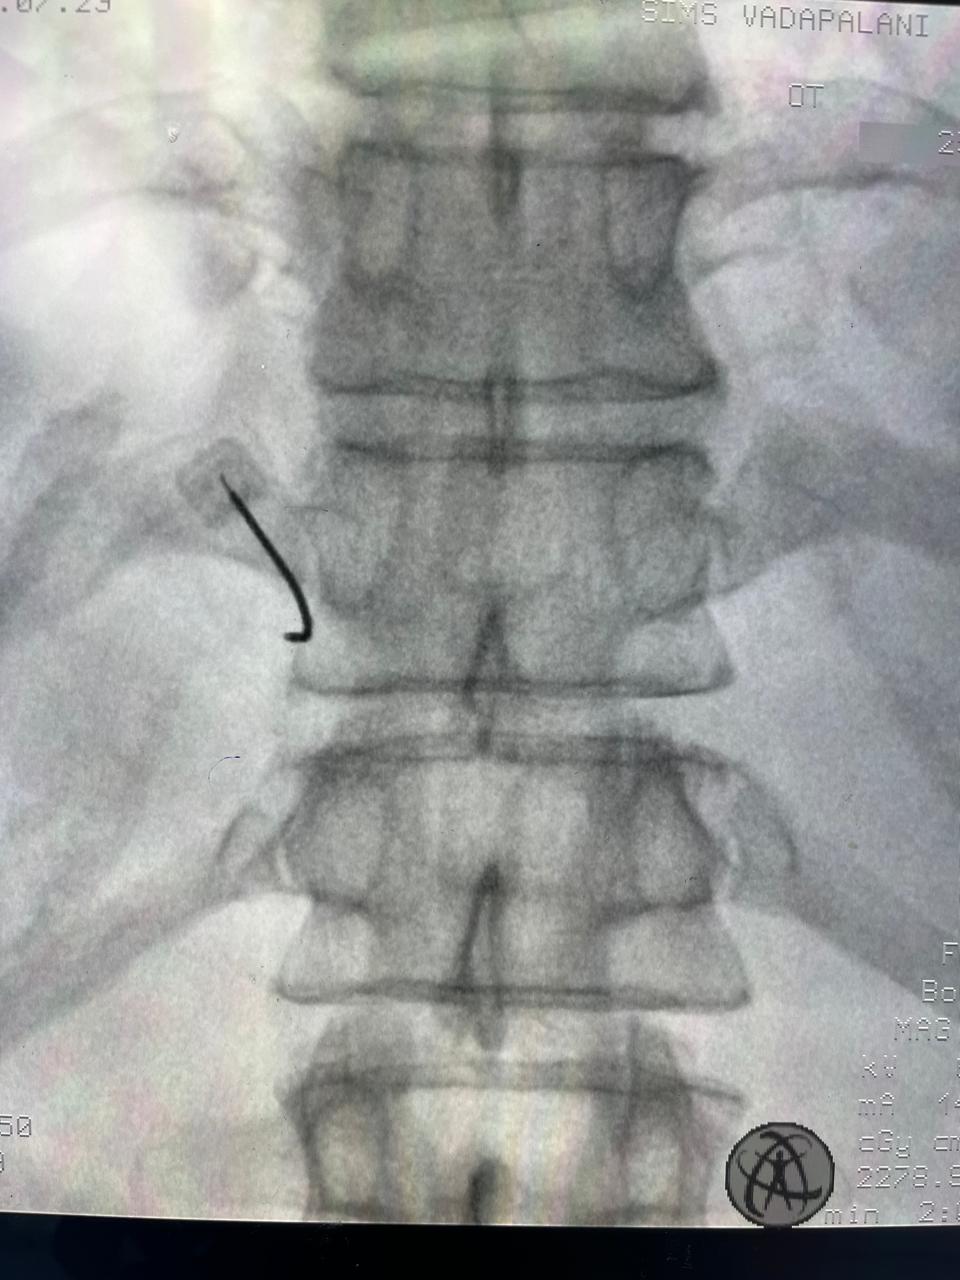

At RK Pain Management Clinic, we are dedicated to providing comprehensive, compassionate care to individuals suffering from chronic pain.